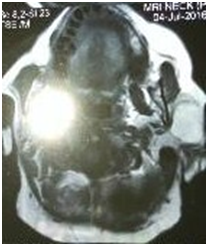

A 52years female presented with painless lump on the left side of face for last 9years. The onset of this swelling was insidious and there was no history of previous trauma. Clinical examination revealed a well defined swelling firm in consistency (Figure 1). At one place near the zygomatic arch the consistency felt to be hard. There was no cervical lymphadenopathy. The most probable clinical diagnosis was mixed parotid tumour or lipoma. Ultrasound examination revealed a hypoechoic, well circumscribed and lobular swelling in the superficial lobe of left parotid gland. Magnetic resonance scan revealed a low density mass in the left parotid gland (Figure 2) (Figure 3). FNA Fine needle aspiration cytology confirmed diagnosis of lipoma. A preauricular incision was made and parotid capsule was incised. The thinned out superficial lobe of parotid was separated giving exposure to lipoma. The branches of facial nerves were set aside. There was a well encapsulated bilobed lipoma in the parotid gland (Figure 4). The larger lobe was of size 9x6x3cm in the superficial lobe while in confluence the small lobe was 2x2cm size and present in the deep lobe. This bilobed yellowish mass was fully exposed and then enucleated. The raised superficial lobe of parotid gland was repositioned and wound closed over a mini negative suction drain. Postoperative recovery as well as follow up has been uneventful. The facial nerve functions were intact. There was no recurrence after nine months of follow up. Histopathology report of this specimen was consisting of mature adipose cells containing clear distended vacuolar cytoplasm and flattened small peripheral nuclei (Figure 5). The mass was well encapsulated lipoma.

Figure 2 MRI showing Bilobed Sialolipoma.

Figure 3 MRI showing Left Parotid Lipoma.

The sialolipoma of the parotid gland has been reported in both superficial and deep lobes. The occurrence of bilobed lipoma in the parotid gland involving both superficial and deep lobes is extremely rare and difficult to differentiate clinically from other parotid tumours particularly Warthim’s tumour. Only a very few cases of giant bilobed sialolipoma of parotid gland have been reported. Radiological imaging modalities are quite accurate in providing the preoperative diagnosis. Ultrasound examination, computed tomography (CT) and magnetic resonance imaging (MRI) can prove to be diagnostic for parotid lipoma. The lipomas have the typical characteristics of homogenous masses with few septations on CT scan. MRI can accurately diagnose lipoma by comparison of signal intensity on T1 and T2 weighted images. There is marginal black rim around lipoma which differentiates it from surrounding adipose tissue. MRI is the best imaging technique for diagnosis and localization of sialolipoma.8 In this case report, preoperative diagnosis of bilobed sialolipoma could be made on ultrasonography and MRI. Fine needle aspiration (FNA) is also diagnostic for parotid tumours but its accuracy rate is 50% for sialolipoma. The tissue diagnosis of sialolipoma of parotid was given accurately on FNA.9